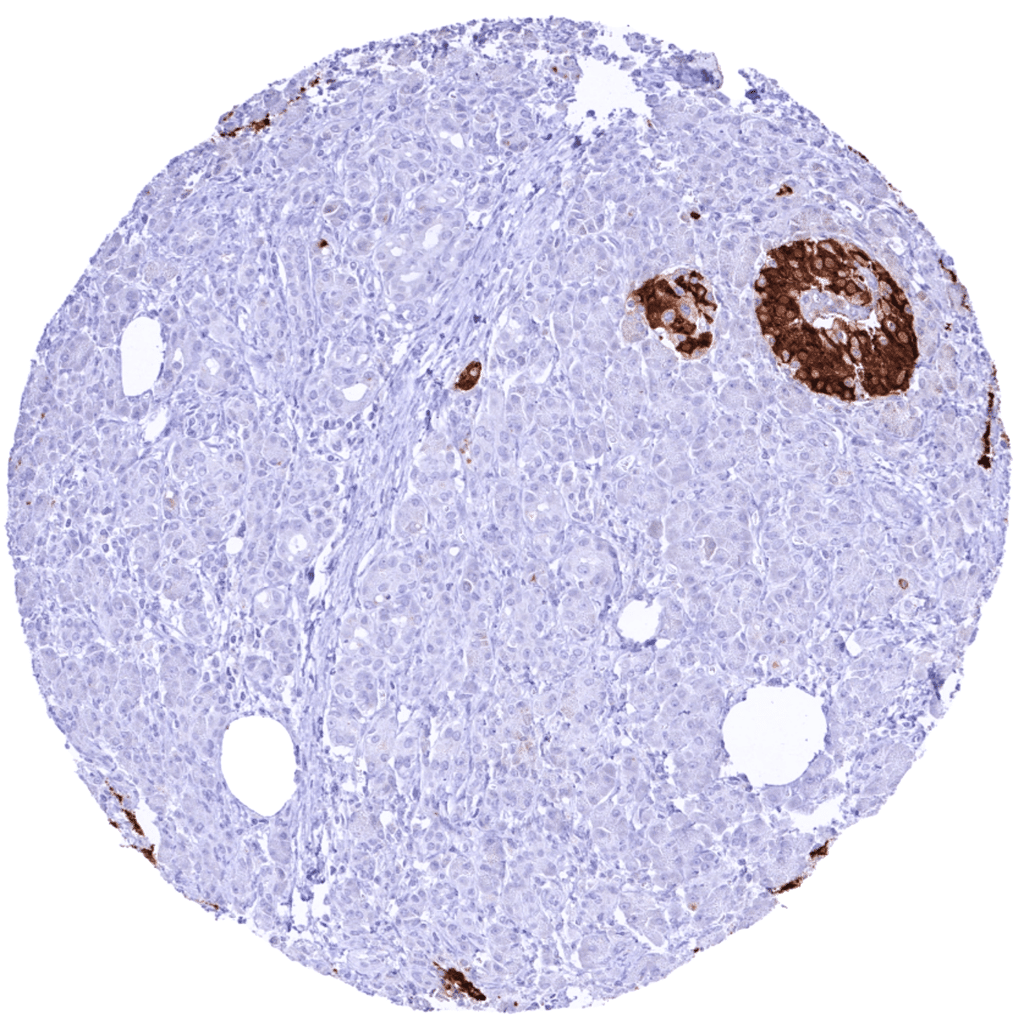

Positive control = Pancreas: A strong C-Peptide staining should be seen in a large fraction of islet cells.

| Pancreas | Strong cytoplasmic C-peptide immunostaining of the majority of islet cells. A faint staining of acinar cells surrounding pancreatic islets can be seen because of „contamination artifacts“. | |

In normal tissues, C-peptide is only produced in islet cells of the pancreas

Negative control = Colon: C-peptide staining must be absent in all cell types.